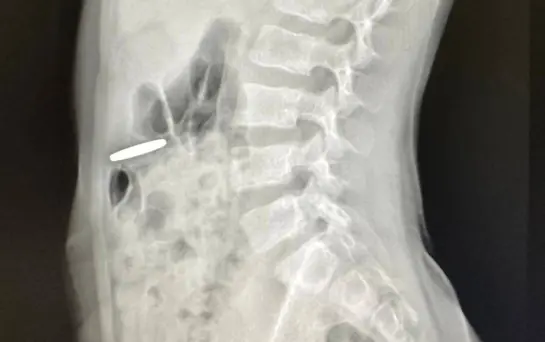

- Мальчик проглотил монетку. При рентгенографии монетка обнаружилась в пищеварительном тракте. Исследование указывало, на то, что монета не двигалась, поэтому в отсроченном порядке ребенку провели эндоскопию и успешно удалили инородное тело, - сообщили врачи.

Инородным телом оказалась киргизская национальная валюта - монета достоинством 10 сом. Сейчас «глотатель» денег чувствует себя хорошо и уже выписан домой.

фото: клиника Рошаля